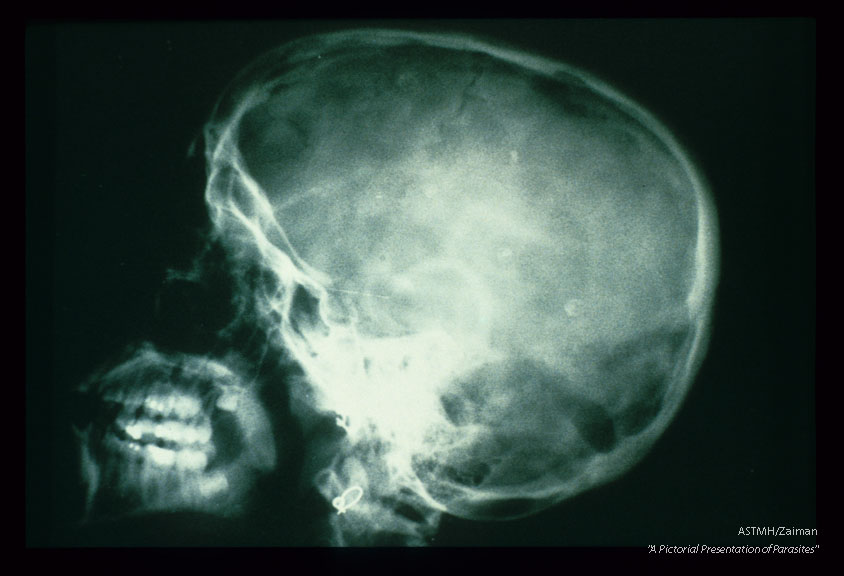

A lateral view of the skull shows multiple small amorphous punctate white calcific masses in the brain. These are calcined cysticerci. Some of these lesions are remarkable for presenting in a target-like configuration. The outer line represents calcification of the bladder wall. The inner dot is the calcified scoiex. The dark area surrounding the scolex is fluid.

Taenia solium